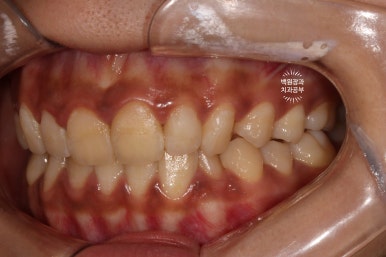

앞니 레진은 워낙 변색으로 악명이 높기에.. 약간은 긴장을 하면서 본 환자분의 입 안은....

상당히 잘 유지되고 있다는 것을 볼 수 있었습니다!

저희 치과에서 색조 안정성이라고 부르는데요.. 3년이 지난 시점까지도 이렇게 색상이 잘 유지되고 있는 3M 레진.... 역시 미국제 대기업 제품은 다르다 생각이 들었습니다.

흡연을 여전히 하고계셨고, 3년만에 내원하여 잇몸 속의 치석이 관찰되긴 하였지만 전에 비하면 훨씬 관리가 잘 되고 있었습니다.

기쁜 마음에 열심히 스케일링을 해드렸어요!! 그리고 1년이 지난 지금도 환자분은 오지 않고 있긴 합니다 ^^;;;